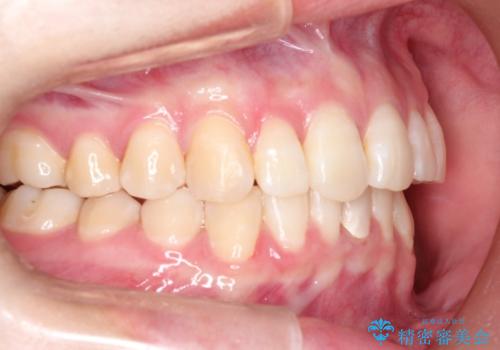

ハーフリンガル ワイヤー矯正による非抜歯・過蓋咬合の治療

- 非抜歯、大臼歯遠心移動による臼歯関係の是正・過蓋の改善をハーフリンガル・ワイヤー矯正にて計画した。